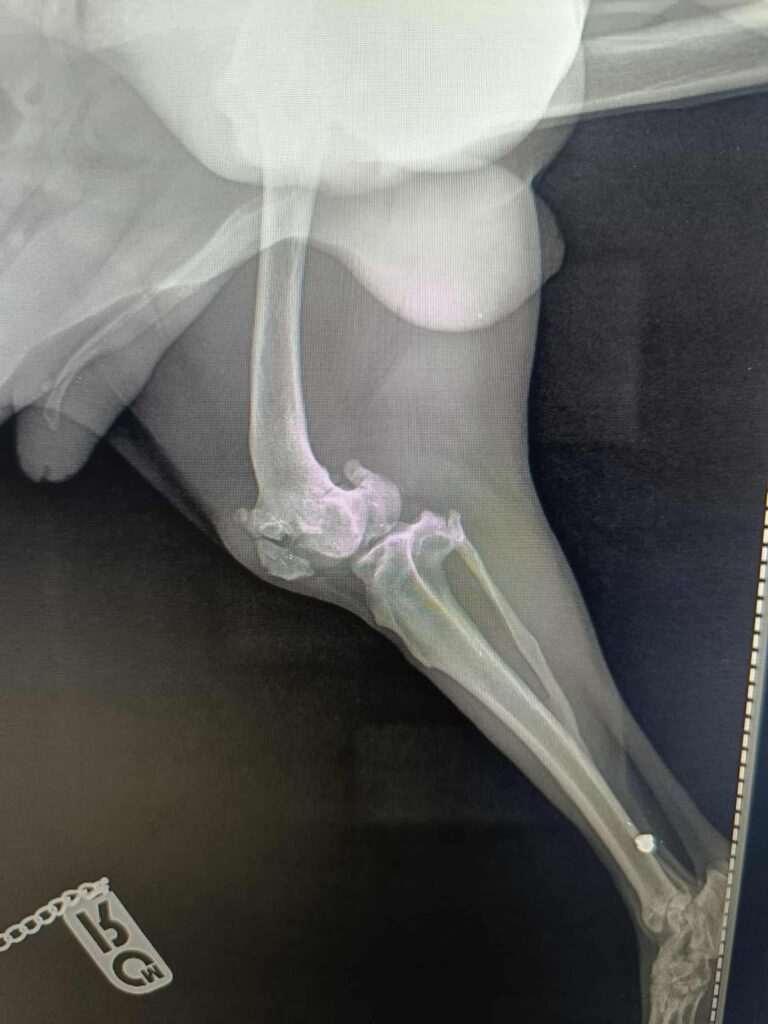

Hij werd aangereden en brak zijn poot.

Niemand deed daar wat aan dus hij heeft daar maanden of misschien wel langer mee rondgelopen.

Inmiddels is de breuk oud en is er niets meer aan te doen.

Roby heeft ook resten van kogels in zijn poot en bekken dus er is ook nog op hem geschoten .

Hij werd aangereden en brak zijn poot.

Niemand deed daar wat aan dus hij heeft daar maanden of misschien wel langer mee rondgelopen.

Inmiddels is de breuk oud en is er niets meer aan te doen.

Roby heeft ook resten van kogels in zijn poot en bekken dus er is ook nog op hem geschoten .

Oude breuk en kogels